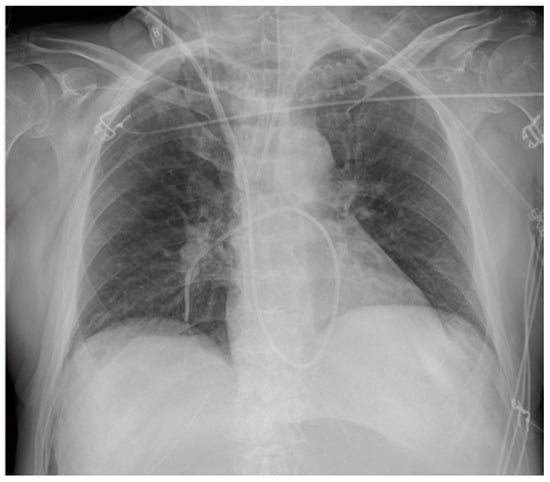

| Bronchus cannulation | Contralateral atelectasis, ipsilateral overinflation (risk of barotrauma, pneumothorax) | |